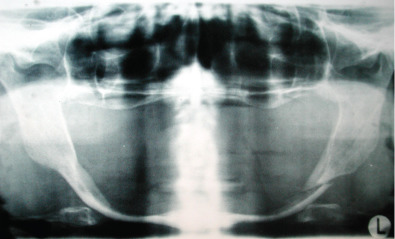

If maxillofacial trauma is suspected, radiographs will most likely be performed. Plain films of the maxillofacial region such as the mandible series, Waters view and submental vertex view are almost always now being replaced by the computed tomography (CT) scan. CT scans of the maxillofacial region give much better detail in a 3-dimensional aspect to assist the provider in diagnosing the injury and formulating a treatment plan. Occasionally, patients seen in the outpatient office will have an orthopantomogram (panorex) as a screening film for mandibular trauma. The orthopantomogram should have another radiograph in a second plane such as an AP film or CT scan to fully assess the injury. A CT scan is the optimal study to assess maxillary and upper face trauma. Additionally, the CT scan can be carried through the skull to assess bony and soft tissue injuries to the central nervous system and cervical spine ( Figs. 1.21.3–1.21.6 ).

Mandible Fractures